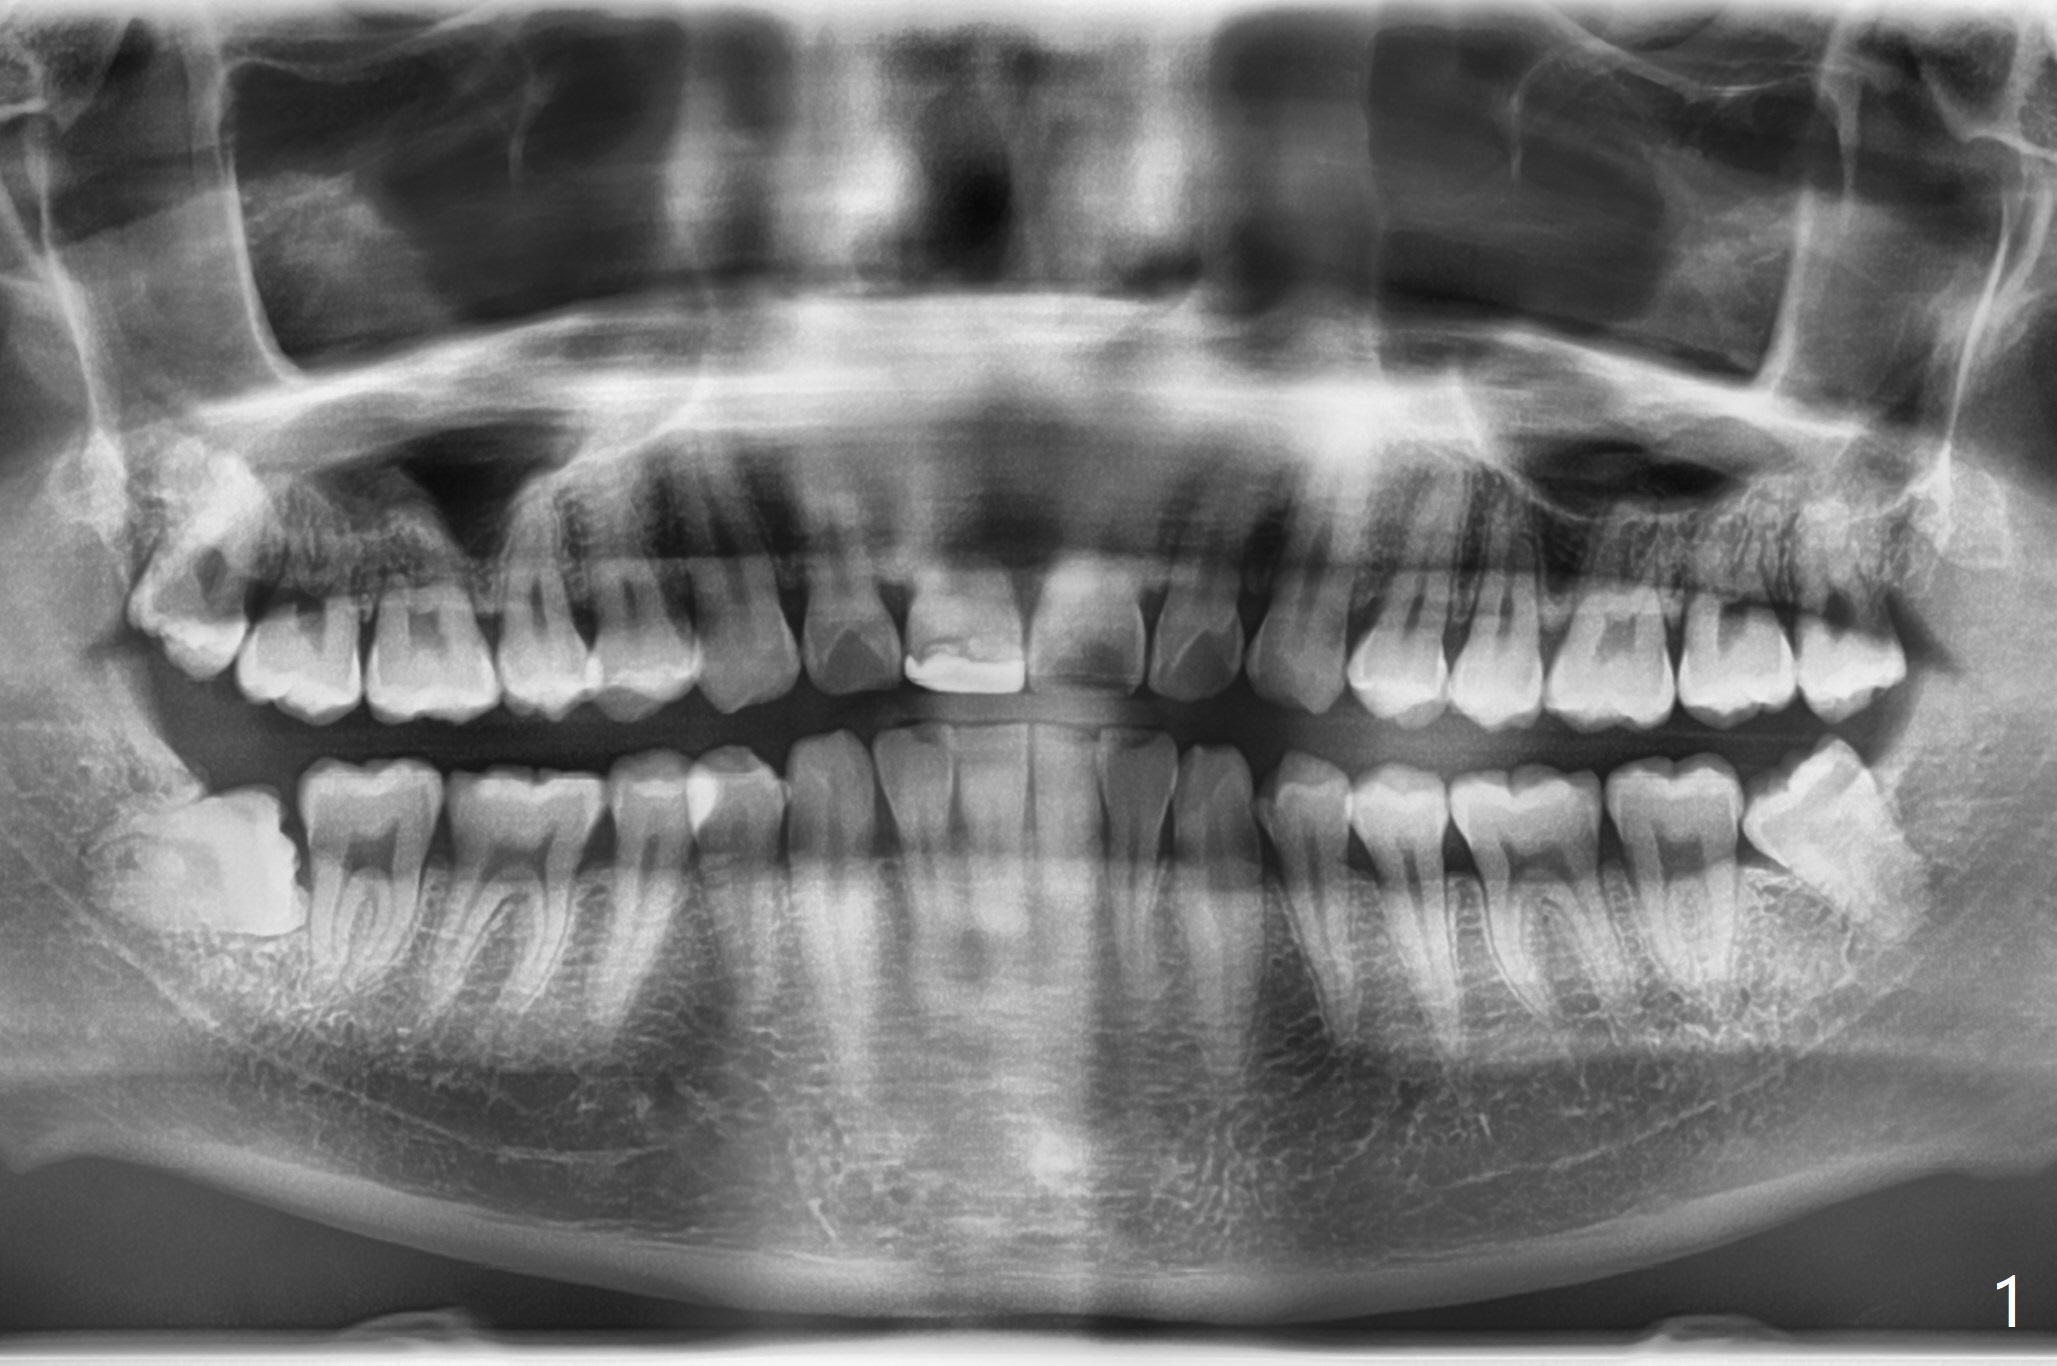

25岁男,特别紧张,要求先拔除左侧智齿(图一,十)。左下牙槽窝放置骨胶原塞。